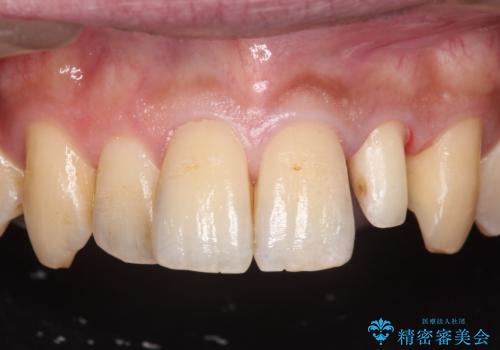

ジルコニアクラウンについて

ジルコニアクラウンは表面がツルツルして

汚れ(細菌)や着色がつきにくいです。

ジルコニアクラウンスペシャルはジルコニアクラウンスタンダードに比べ

色のバリエーションが多く、よりご自身の天然歯の色と合うように作れます。

自然な被せ物が入り、大変満足して頂けました。